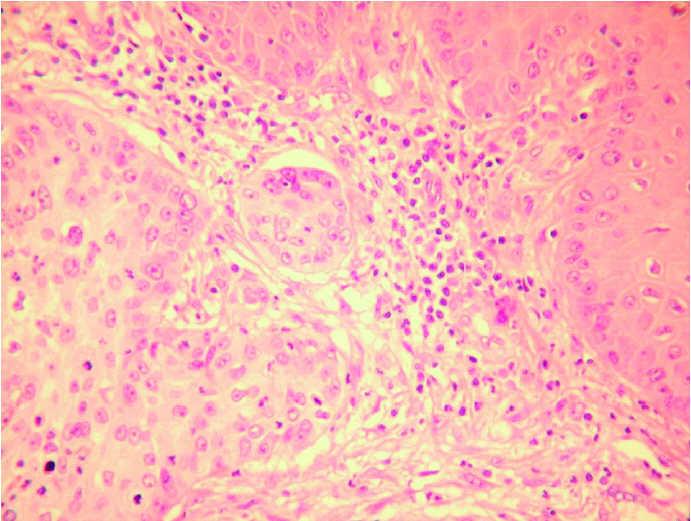

Un varón de 88 años, con antecedentes de demencia e hipertensión arterial, consultó por la aparición de una lesión muy dolorosa, de 3 meses de evolución, en el primer dedo del pie izquierdo, de rápido crecimiento. Había realizado tratamiento con antibióticos tópicos y orales sin mejorar. En la exploración se observaba una placa ulcerada, rojiza y exudativa que afectaba el extremo distal del dedo con destrucción ungueal (fig. 1). Con la sospecha de tumor maligno primario o metastásico, se realizó estudio radiológico y biopsia. En la radiografía se observaba una lesión lítica que destruía totalmente el extremo de la falange distal del primer dedo respetando la articulación interfalángica, apoyando el diagnóstico de un tumor maligno (fig. 2). En el estudio histológico, la epidermis estaba ulcerada parcialmente y a nivel de la dermis se evidenciaba una proliferación de células neoplásicas de aspecto epitelial, con abundantes mitosis y atipia nuclear (figs. 3 y 4). Algunas de estas células eran positivas con la tinción con ácido peryódico de Schiff (PAS). La tinción con citoqueratinas fue positiva. Ante la posibilidad de que se tratara de una metástasis acral, se realizó tomografía computarizada (TC) toracoabdominopélvica en la que se objetivó una gran tumoración de más de 7 cm de diámetro en el lóbulo inferior izquierdo, un nódulo de 1 cm en el lóbulo posterior derecho compatible con metástasis y adenopatías hiliares. El estudio abdominopélvico fue normal. Con estos datos se realizó el diagnóstico de carcinoma de pulmón con metástasis digital acral. Debido al intenso dolor que provocaba la metástasis se amputó el primer dedo del pie. El paciente falleció a las pocas semanas.

Fig. 3.--En la biopsia cutánea se observa una epidermis ulcerada y una proliferación de células neoplásicas de estirpe epitelial en la dermis. (Hematoxilina-eosina, ×100.)

Fig. 4.--A mayor aumento se evidencian abundantes figuras de mitosis y atipias celulares. (Hematoxilina-eosina, ×200.)